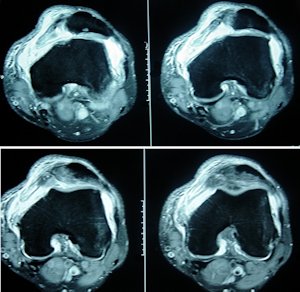

Sonuç olarak, akut patella çıkığı sonrasında büyük osteokondral lezyon, devam eden patellar subluksasyon varsa ve anatomik risk faktörleri belirgin ise cerrahi tedavi seçilmelidir. (Resim 3 ve 4).